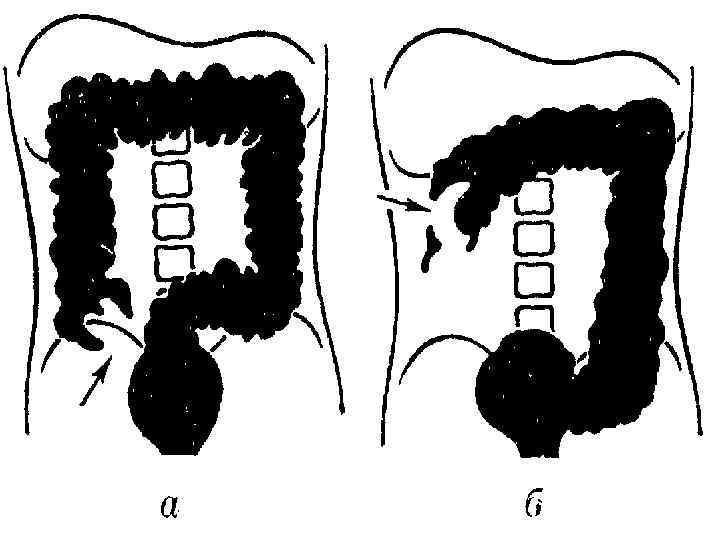

Клиническая картина Основные симптомы: Боль без четкой локализации, схваткообразная или постоянная с разной степенью интенсивности. симптом Тэвенара – боль при пальпации на 2 поперечных пальца ниже пупка(проекция корня брыжейки тонкой кишки). При странгуляционной непроходимости. вздутие живота – может быть симметричным и ассиметричным(странгуляционная). Характерно для высокой непроходимости. видимая перистальтика – характерна для механической непроходимости. Рвота – многократная, ненадолго приносящая облегчение, переходящая постепенно в каловую рвоту. симптом Валя – высокий тимпанит над проекцией толстой кишки – характерно для ранней механической непроходимости. симптом Шимана – западение живота в левой подвздошной области, в то время как в правом подреберье вздутие толстого кишечника, при завороте сигмовидной кишки. симптом Склярова – шум плеска при сукуссии. симптом Спасокукоцкого Вильмса – шум падающей капли, растянутые петли кишечника. Аускультация живота, по образному выражению наших хирургических учителей, необходима для того, чтобы «услышать шум начала и тишину конца» (Г. Мондор). «гробовая тишина» отсутствие перистальтики. пальцевое ректальное исследование – «каловый завал» , вздутие ампулы. интоксикационный синдром – температура, тахикардия, головная боль и слабость – признак калового застоя.

Инструментальная и лабораторная диагностика ОАК – эритроцитоз до 5 6 млн. , лейкоцитоз до 20 тыс. со сдвигом лейкоцитарной формулы влево, эозинопения. , повышение значения СОЭ. БХАК снижение уровня хлоридов с 500— 550 мг% до 400— 300 мг%, повышение остаточного азота, возможно повышение ALT AST CРБ. ОАМ – снижение количественного показателя, повышение концентрации белка. Обзорная рентгенография – наличие «кишечных арок» , «чаши Клойбера» , симптом перистости(растяжение тощей кишки). Ирригоскопия – симптом «трезубца» , видимые нарушения проходимости. Колоноскопия – визуальное определение патологии. УЗИ КТ